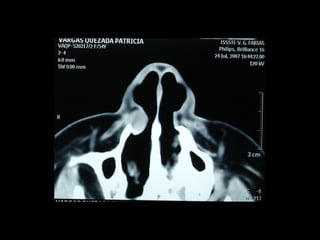

Quiste seno maxilar